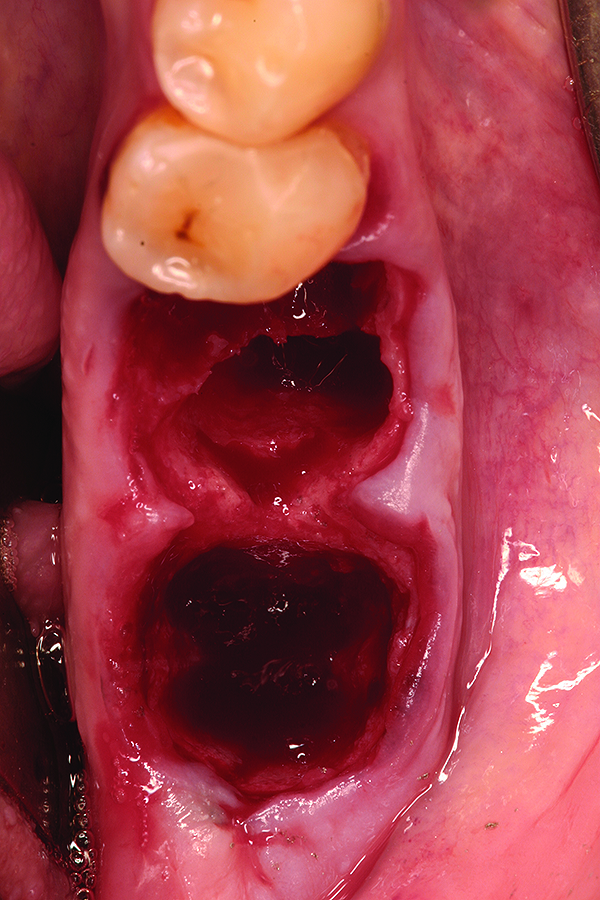

Fig 10. Placement of bone allograft into extraction site with collagen membrane on buccal aspect for graft containment.

Figure 10

Fig 11. Intentional non-primary closure following the placement of an amnion-chorion barrier over the bone allograft.

Figure 11